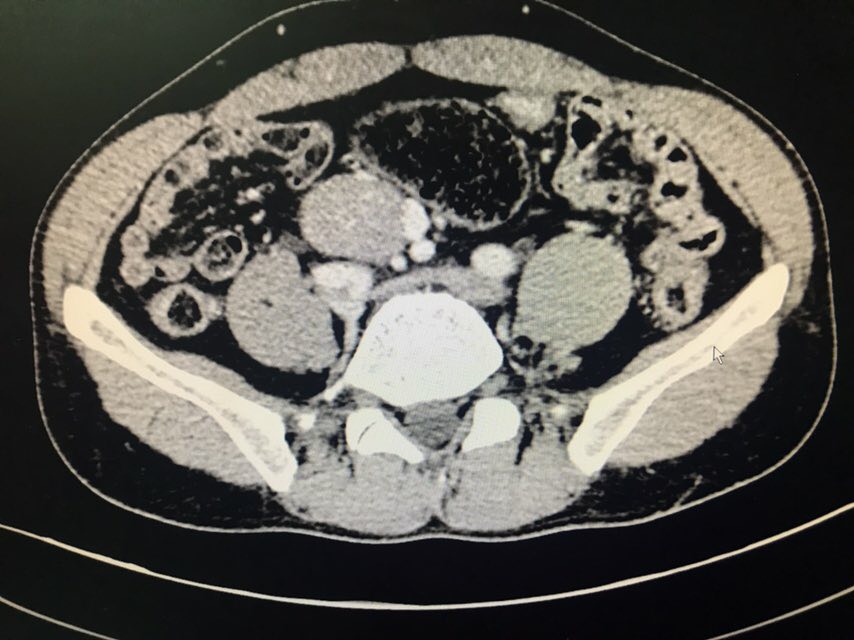

患者男性,43岁。主诉:发现盆腔占位1+月。现病史:患者1+月前于当地医院体检发现盆腔包块,于2018-08-28我院行泌尿系超声示:右侧髂窝实性占位伴钙化;2018-08-31我院行CT下腹部盆腔增强扫描示:下腹部及盆腔内多个软组织结节肿块影,肝右后叶上段囊肿;2018-09-07我院行病理检查示:盆腔肿瘤,倾向神经内分泌肿瘤,需行免疫组化染色检查;2018-09-07我院行膀胱超声示:超声引导下膀胱右侧盆腔内实性团块CNB。现患者为求手术治疗,于我院门诊就诊,以“盆腔肿瘤”收入我科。既往史无特殊。

查体:双侧腰部外形对称,皮肤无红肿,双肾区无叩痛,双肾下极未扪及,双输尿管行程区无压痛,膀胱区无隆起及压痛。双侧腹股沟区未扪及异常,无压痛;阴囊及尿道口未查。辅助检查:泌尿系超声(2018-08-28本院):右侧髂窝实性占位伴钙化;CT下腹部盆腔增强扫描(2018-08-31本院):下腹部及盆腔内多个软组织结节肿块影,肝右后叶上段囊肿;病理检查(2018-09-07本院):盆腔肿瘤,倾向神经内分泌肿瘤,需行免疫组化染色检查;膀胱超声(2018-09-07本院):超声引导下膀胱右侧盆腔内实性团块CNB。

诊断:盆腔肿瘤治疗:剖腹探查+盆腔占位切除术

患者膀胱右后方实性占位,穿刺活检倾向神经内分泌肿瘤,有手术指征。术中盆腔占位与周围重要组织器官粘连紧密,完整游离后整个创面较大,手术顺利,术后给予曲克芦丁脑蛋白水解物注射液2ml治疗。等待最终病理结果回报后制定下一步放化疗方案。